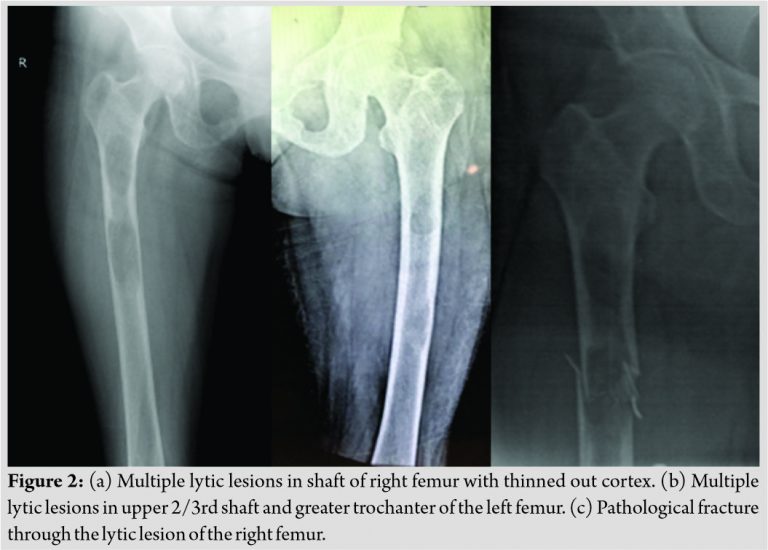

A clinical diagnosis of Osteomalacia with Looser’s zone in pubic rami and incomplete fracture in right femur was considered. Metastatic lesions, multiple myeloma, or hyperparathyroidism with brown tumors were considered as differential diagnoses. The patient underwent X-rays of relevant areas. X-ray of pelvis with both hips (Fig. 1a and b) showed multiple small osteolytic lesions in both ilium and femur, thinning of cortices and uniting fractures in bilateral pubic rami. X-rays of both thighs (Fig. 2a and b) showed generalized osteoporosis, multiple lytic areas of 2–3 cm size separated with each other by a small zone of normal bone in upper one-third of shaft.

There were two large osteolytic areas in the right shaft femur. The patient was admitted for prophylactic nailing in right femur in view of the impending fracture through the lytic areas (Fig. 2a). She was given an above knee up to groin plaster slab and advised bed rest. In the left femur, the osteolytic areas were relatively smaller, cortices were thicker and there was no immediate risk of an impending fracture. Hence, fixation of left femur was not considered. X-rays of skull, chest, lumbar spine, feet, and hands did not show any obvious abnormality. Old magnetic resonance imaging (MRI) of thighs suspected the small lytic lesions in both femora as simple bone cyst. Fresh MRI with contrast (Fig. 3a and b) showed multiple intramedullary solid cystic lesions of varied size in both pubic rami, ischium, iliac blades, and upper and middle one-third of both femora probably due to browns tumor.

While indoor, the patient tried going to bathroom and fell down, leading to fracture through the lytic area in the right proximal femur (Fig. 2c). The fracture was surgically stabilized with long proximal femur nail and static locking (Fig. 4a).